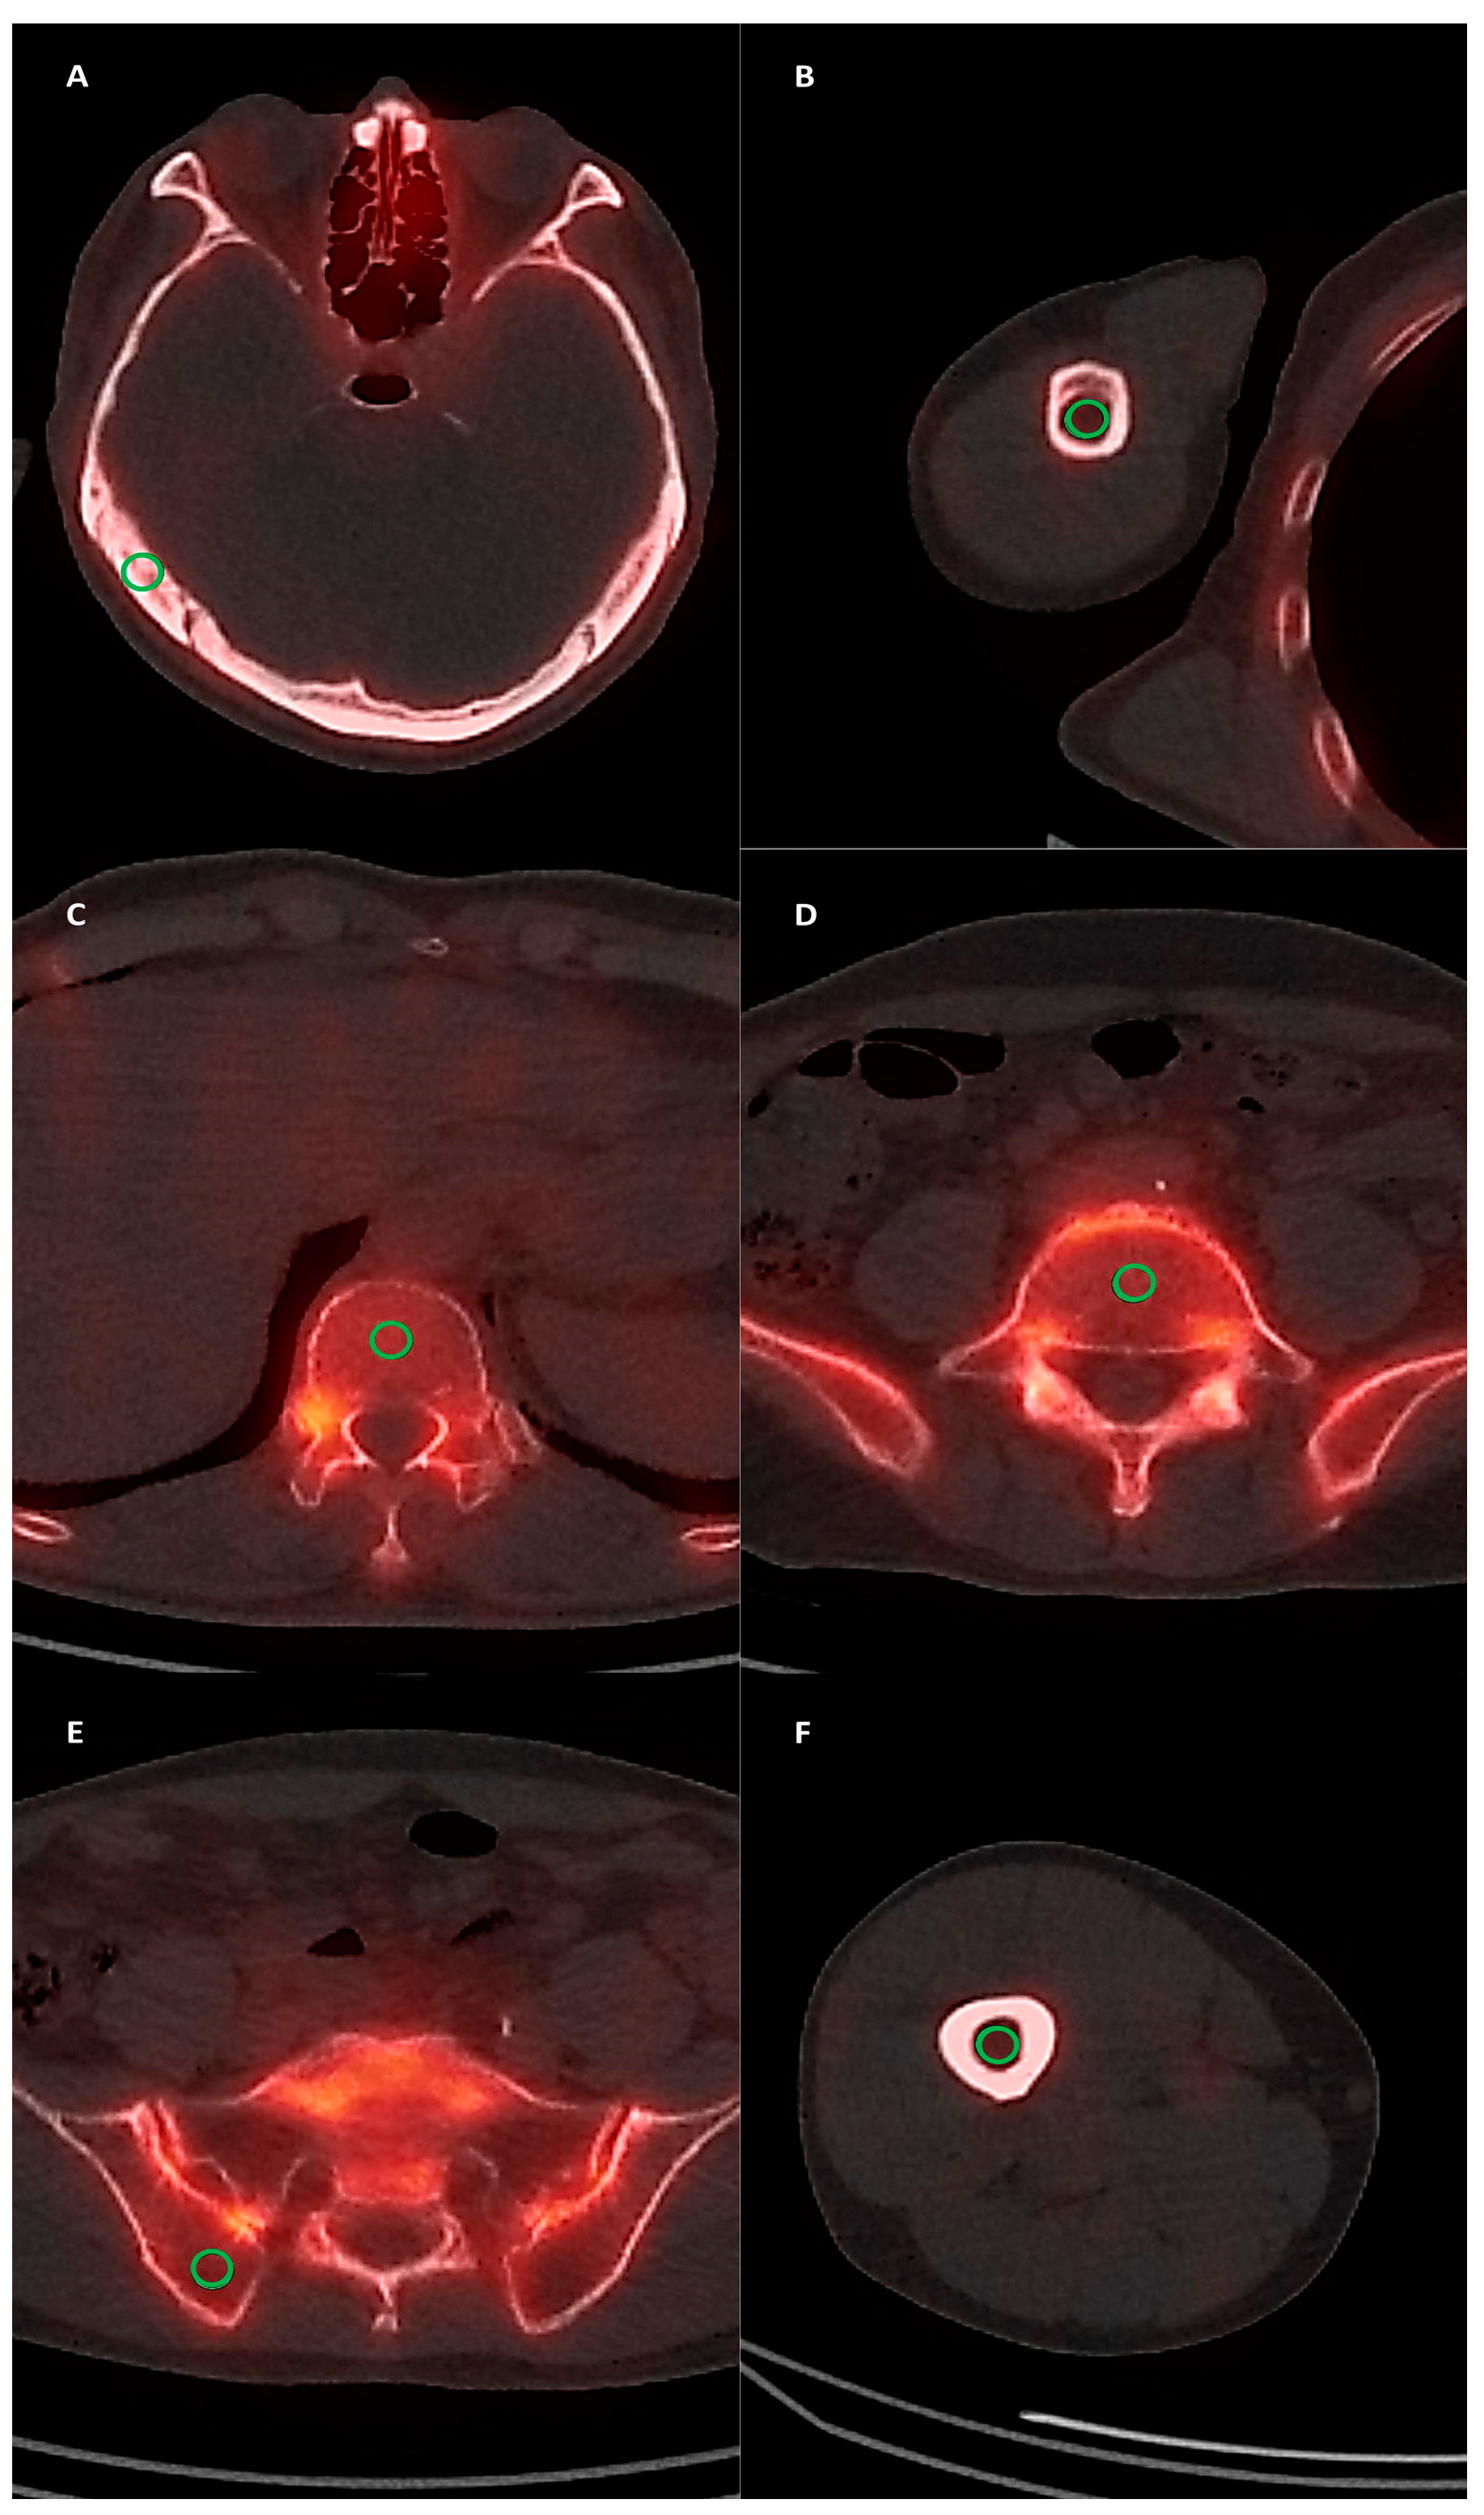

2.3. SPECT/CT Image Analysis

3.3. Diagnostic Ability of SPECT/CT Imaging Parameters